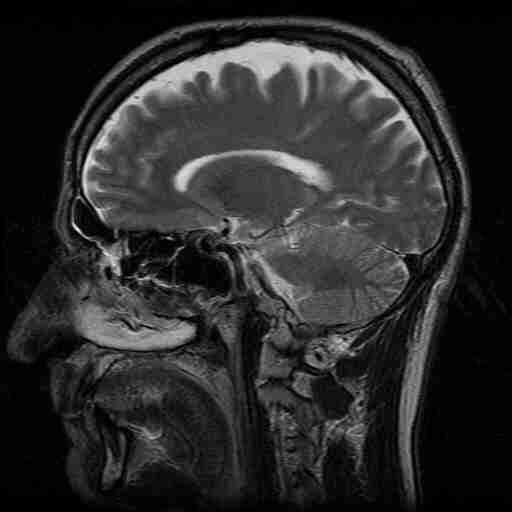

MRI is perhaps the most useful type of tomography, providing excellent anatomical images without exposing patients to potentially harmful radiation. Figure 18 shows an MRI cross-section of the head.

Figure 19:MRI of the head.